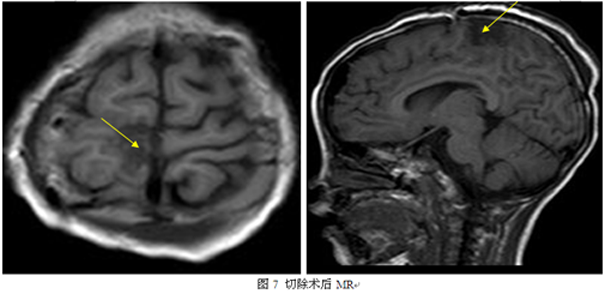

经我院癫痫中心讨论认为患者致痫区可能位于右侧旁中央小叶,因其位于重要功能区且界限不清,建议行颅内电极植入明确致痫区以及通过皮层电刺激明确功能区,遂在全麻下行右侧额顶中央区脑深部电极置入术,手术过程顺利,术后行颅内电极视频脑电图监测提示间歇期:癫痫样放电,多脑区性,Y’4-9、N’4-9著;发作期:临床:左下肢强直→左下肢强直-阵挛;EEG:发作型,Y’4-9、N’4-9(其中Y’:中央后沟—中央后回—中央旁小叶后部(缘支前壁);N’:中央后回—中央沟—中央前回—中央旁小叶(病变)见图3、图4),术后电刺激结果见图5.根据监测结果和电刺激结果确定切除范围(如图6)。并在全麻下行右侧旁中央小叶区癫痫灶切除术,术中结合电生理监测和导航确定中央沟、中央前沟及中央后沟等重要解剖结构,按术前切除计划切除右侧旁中央小叶(见7),术后病理检查提示为皮质发育不良(FCD IIa)。术后查体左侧肢体肌力二级,予以加强康复等治疗,术后第四周,患者左侧肢体肌力肌张力恢复正常,无癫痫发作,现已恢复出院。